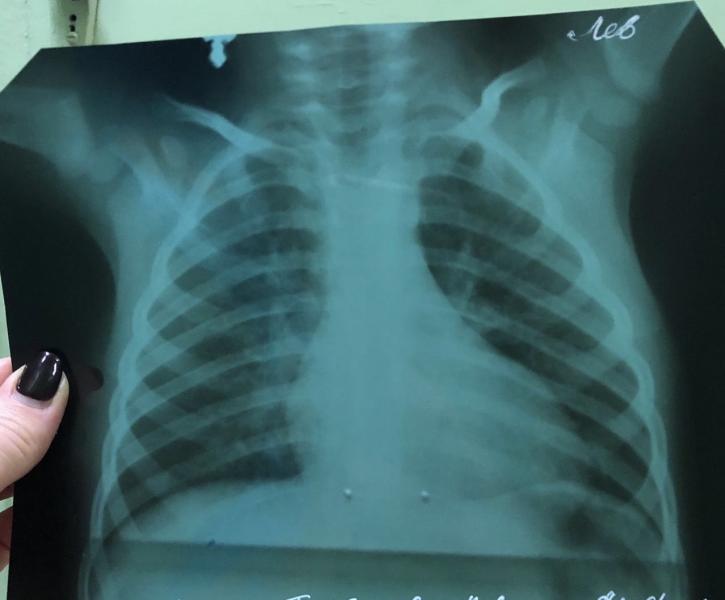

Ребёнку ставят пневмонию под вопросом, сделали снимок и сдали кровь, сегодня были в больнице, вроде хрипов нет, по снимку ответ дадут в пн, сказали кровь хорошая и отправили домой. Два врача сказали кровь хорошая без воспалений, а один врач сказал кровь плохая, езжайте госпитализироваться. Что делать???

У вас признаков воспаления в крови нет, есть микроцитарная анемия, вероятно, железодефицитная. Анемия лёгкой степени, возможно, для такого возраста вариант нормы, точно не могу сказать про ребенка)) но с пневмонией уж точно не связана. По рентгену отчётливо нет инфильтрации.